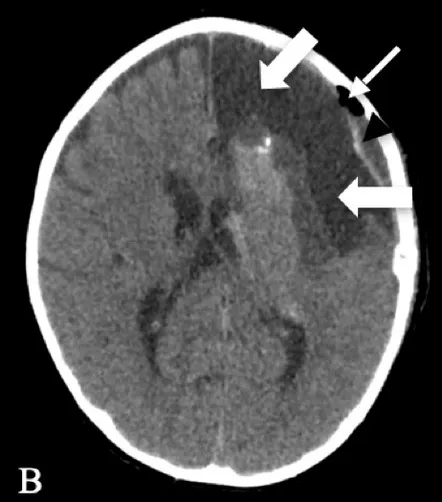

| Patient 2 | Pathology: Large cortical malformation of the left hemisphere (white oval on axial T2-MRI, Figure A1). |

|

| F, 2 years | Seizures: Daily asymmetric spasms and right hemifacial seizures | ||

| Neurological examination: Normal | |||

| Surgery: IONM during extensive frontal lobectomy up to the motor cortex; and temporal disconnection. Early postoperative axial CT scan (Figure B1) demonstrating the cystic cavity on the left frontal (bold white arrow) and small subdural hygroma with air collection (thin white arrows). | |||

| Follow-u p: No motor deficit. Early postoperative seizures with excellent effect of Carbamazepine introduction. | |||